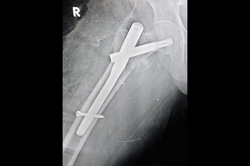

Humerus